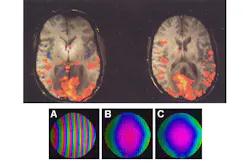

The synthesized RF pulses provide a coherent image (see the figure) compared to the first, conventionally obtained image. The scans were performed in conjunction with a GE Signa EXCITE 3 T MR Scanner. The accuracy of the DAC board provided a reference signal that compensated for the phase of off-resonance frequencies used to excite different slices.